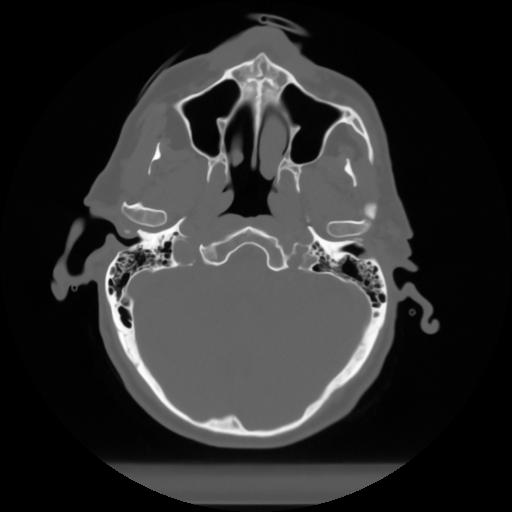

10 P.BLANDAS,,Axial,2.0,P.BLANDAS,,